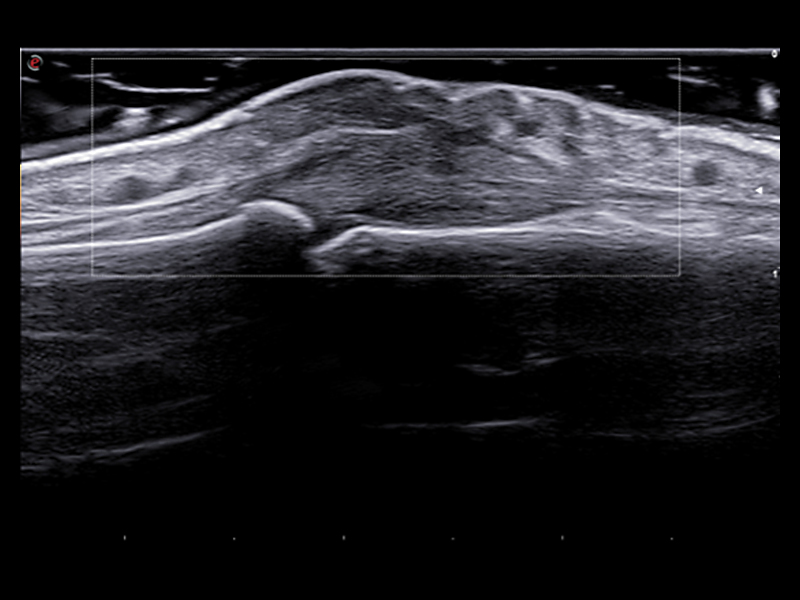

B-Mode utilizing Very-High Frequency probes proves valuable in numerous rheumatic diseases, where exceptional resolution and the ability to visualize details play a pivotal role.

A genuine technological breakthrough in very superficial explorations, the LMX 4-20, Esaote’s brand-new HD Single Crystal probe, offers unprecedented clarity even in the smallest details without compromising the deeper areas. Applied to this high-density element per multi-layer matrix structure array, XCrystal Technology enables unparalleled sharp and clear imaging to achieve excellence in superficial ultrasound examinations and becomes the Esaote gold standard in terms of linear probes.

These arrays, enabling to operate up to 25 MHz, provide outstanding image quality for very superficial scans, such as fingers, elbows, and wrists and, for example, allow accurate evaluation of the hyaline cartilage of the metacarpal head.